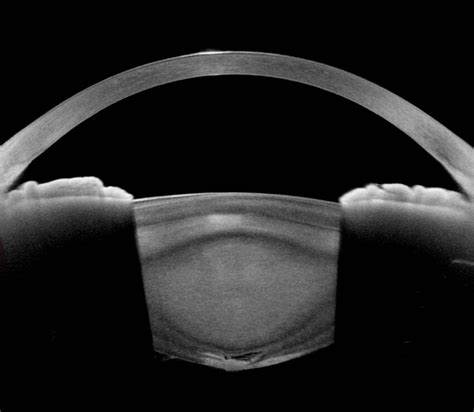

CATARACT SERVICES

• MICS PHACO EMULSIFICATION

• PREMIUM INTRAOCULAR IOL IMPLANTATION

• MULTIFOCAL, ADVANCE MONOFOCAL, TRIFOCAL IOL IMPLANTATION

• SCLERAL FIXATED IOL IMPLANTATION

• ANIRIDIA IOL IMPLANTATION

• CATARACT SURGERY IN HIGH RISK CASES LIKE POSTERIOR POLAR, HYPERMATURE CATARACT, WEAKER ZONULES, NON-DILATING PUPIL, POST UVEITIS CATARACT, POST RETINA SURGERY CATARACT, CATARACT WITH CORNEAL OPACITY UNDER TOPICAL ANAESTHESIA